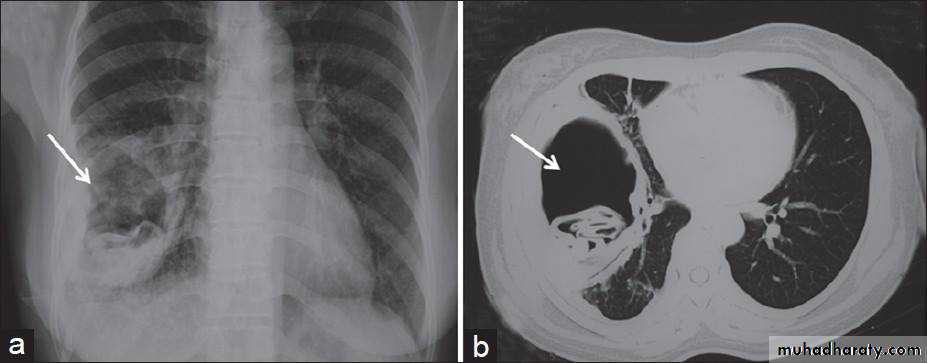

ruptured Hydatid cyst

3/air +nodule :mycetoma( fungus in previous cavity)

Cavity with air fluid level

Air fluid level with membrane (ruptured hydatid cyst )